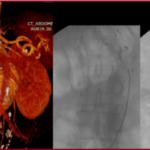

Στένωση Καρωτίδας

Η στένωση καρωτίδας είναι η στένωση της καρωτιδικής αρτηρίας λόγω συσσώρευσης αθηρωματικής πλάκας, η οποία μπορεί να μειώσει τη ροή αίματος προς τον εγκέφαλο και να αυξήσει τον κίνδυνο εγκεφαλικού επεισοδίου.